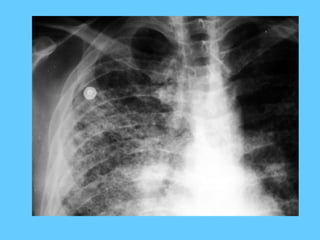

Excessive oxygen in

a respirator circuit